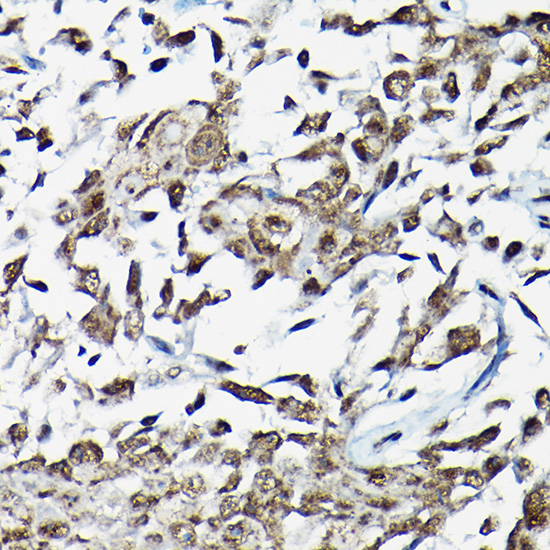

Immunohistochemistry of paraffin-embedded Human urothelial carcinoma tissue using Smad2 Polyclonal Antibody.